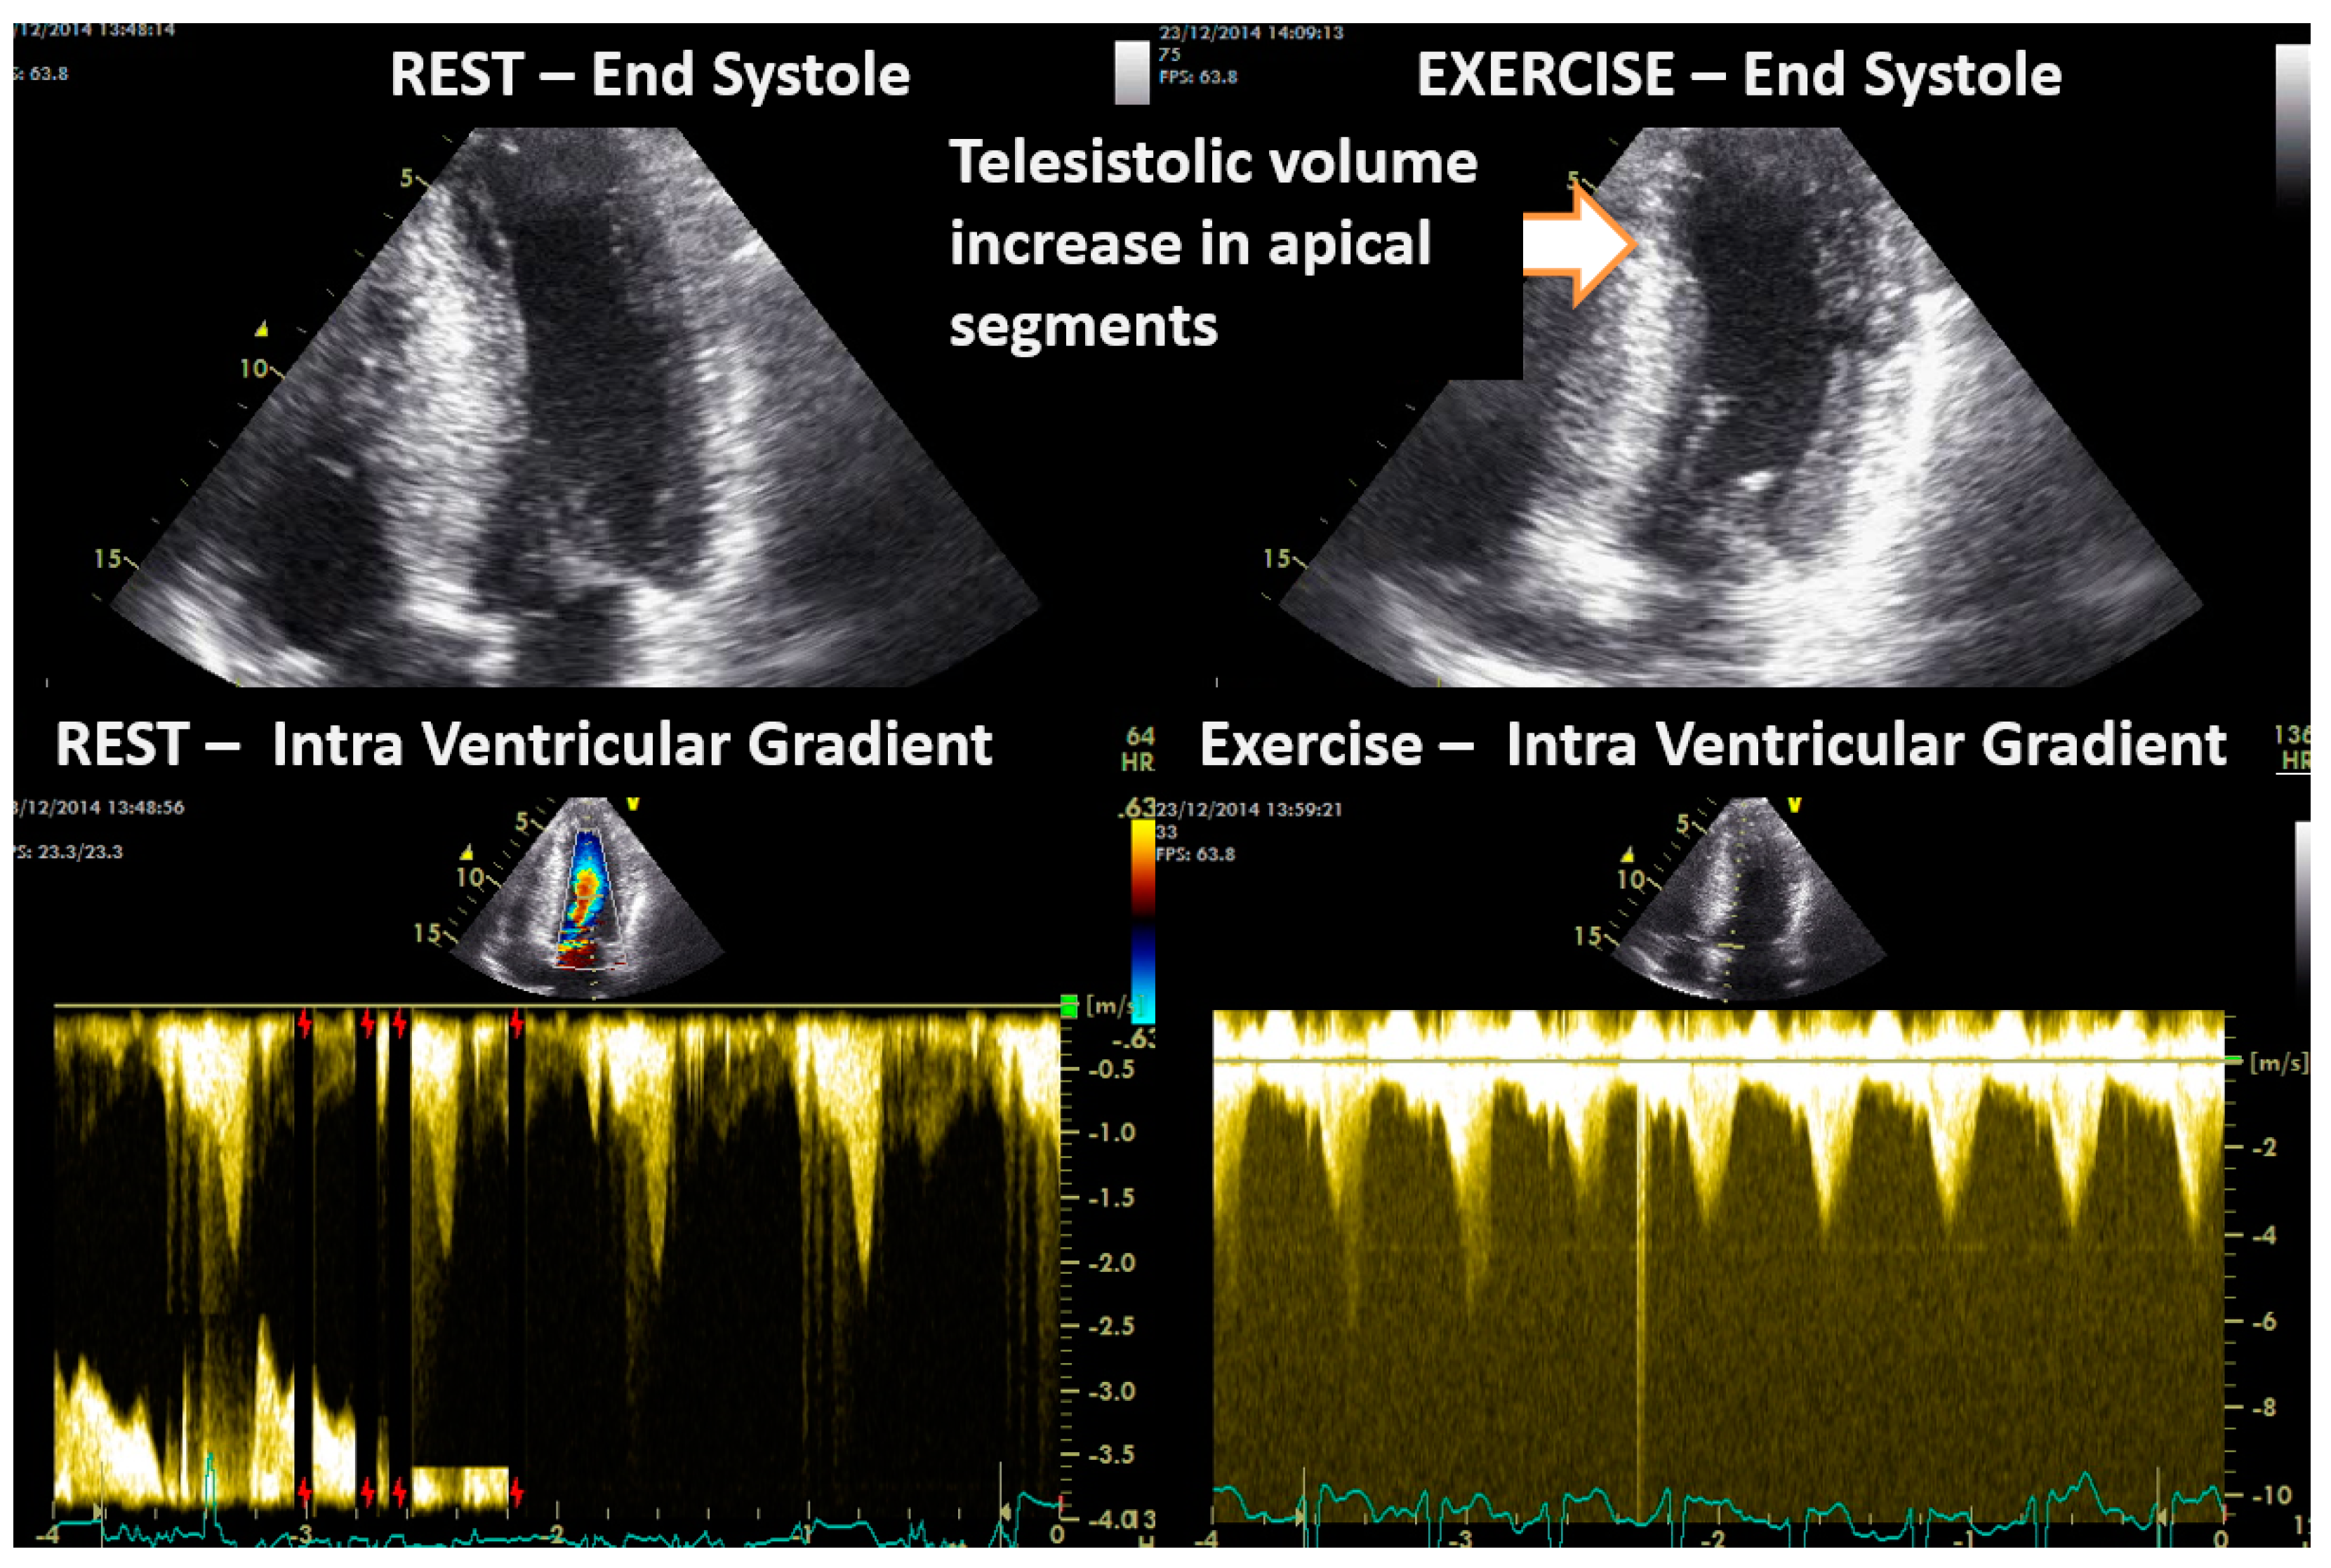

In Group II, the ten children with a diagnosis of HCM were non-obstructive before exercise, and four developed intraventricular obstruction with exercise. One of these four children is a symptomatic young boy whose exercise-induced obstruction was the first sign of HCM, having no hypertrophy at the moment of the ESE [24]. Another developed dilation of the left ventricle, particularly at the level of the apical segments (Figure 6).

Figure 6.

Intraventricular obstruction and contractility alterations during exercise in one symptomatic 16–year-old boy with obstructive hypertrophic cardiomyopathy.